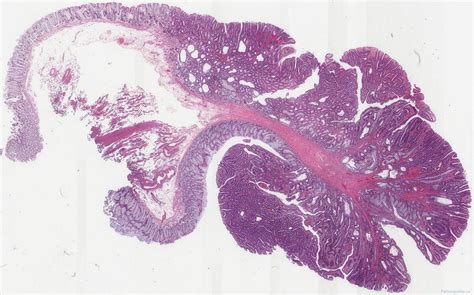

What is a Tubular Adenoma of the Colon?

A tubular adenoma is a type of polyp that forms on the inner lining of the colon. These polyps are composed of glandular tissue and are characterized by their tubular shape. Tubular adenomas are the most common type of adenomatous polyps, which are known to have the potential to become malignant if left untreated. Early detection and removal of these polyps are essential for preventing the development of colorectal cancer.